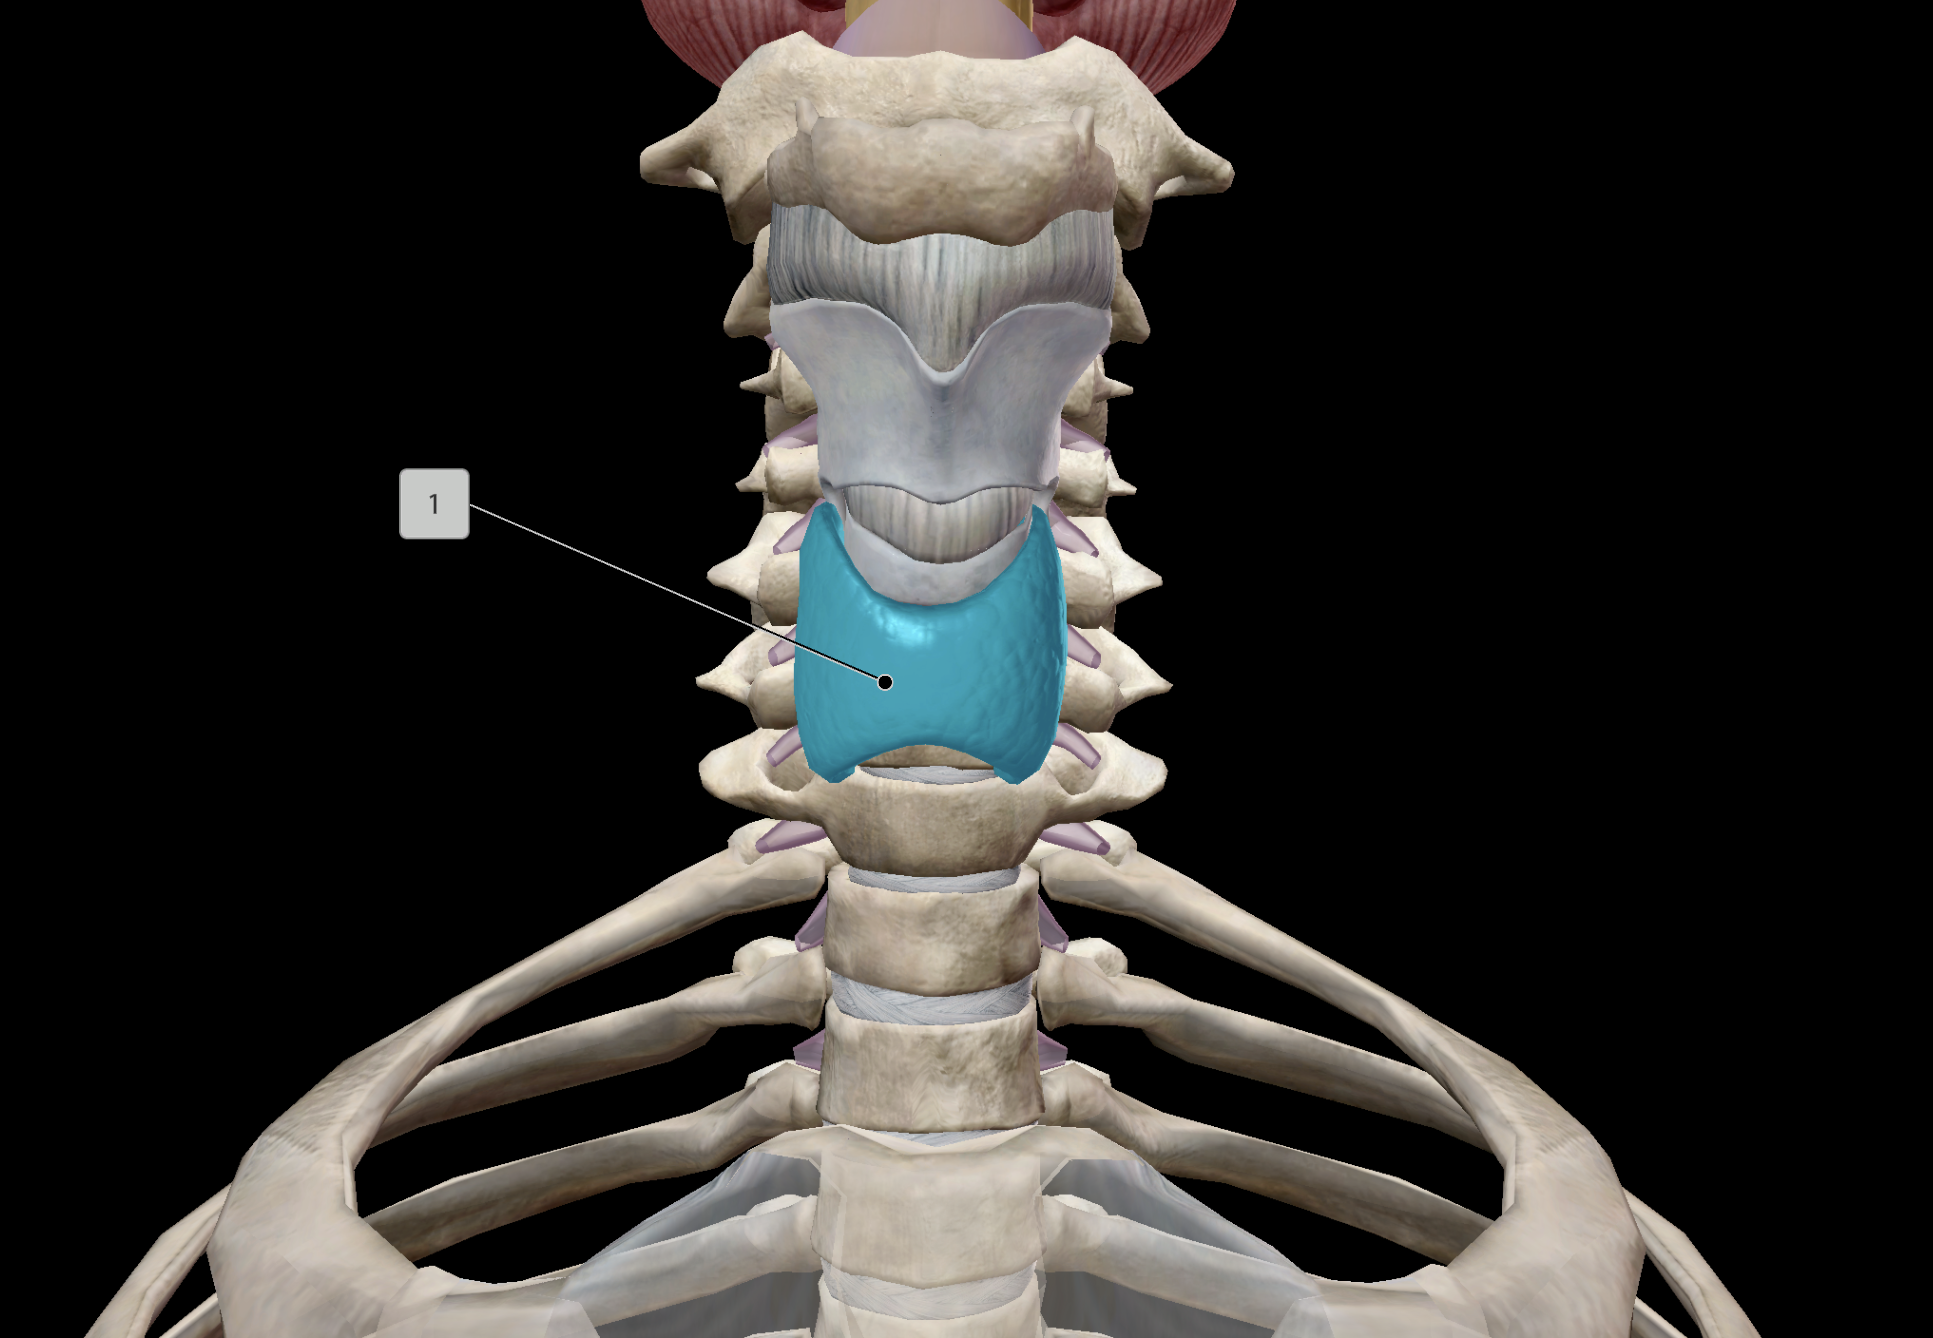

Thyroid Gland